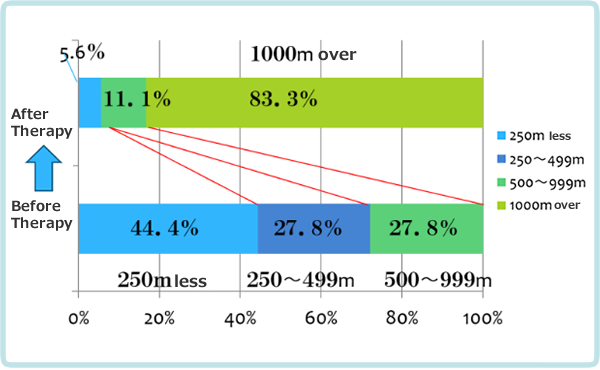

Results

The average number of new meridian therapy was 31.5. The average walkable distance was 324.5 m at the first visit and improved to 2242.6 m at the last visit, a seven-fold improvement. Improvement to 1,000 m or more without pain or numbness was defined as " greatly improved," 500 m to 1,000 m as "moderately improved," 250 m to 500 m as "little improved," and less than that or no improvement as "no change.

83.3% of the patients reported 'very much improved' and 94.4% reported 'much improved' or more (see Figure 2-9). The new meridian therapy is highly effective in improving gait, suggesting that it improves inflammation of the cauda equina nerve, edema of the spinal canal, and blood flow in the spinal vessels.